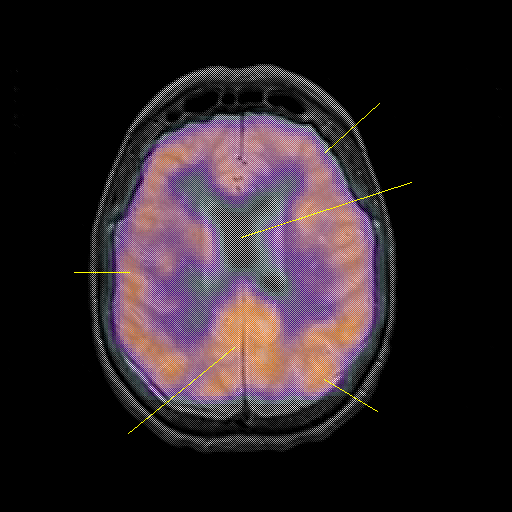

overlay : Slice 35

Slice 35

Pointers

Labeled